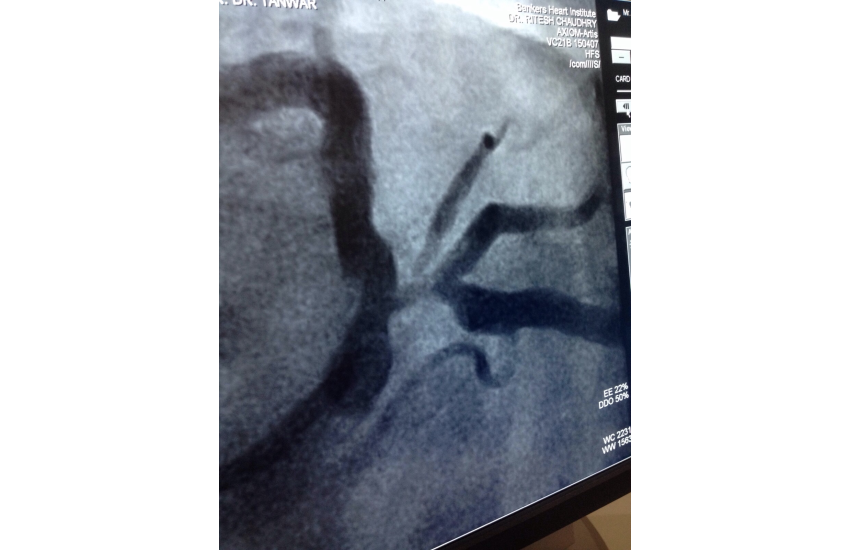

75 years old male presented with unstable angina undergone CAG which is shown LMCA bifurcation lesion first option given for CABG surgery but Pt. is not willing for that so after discussing all the risk of LMCA bifurcation kissing steanting Than patient and relatives ready for that and with all life support system successfully done by Dr N T sir. After steanting patient is doing well.